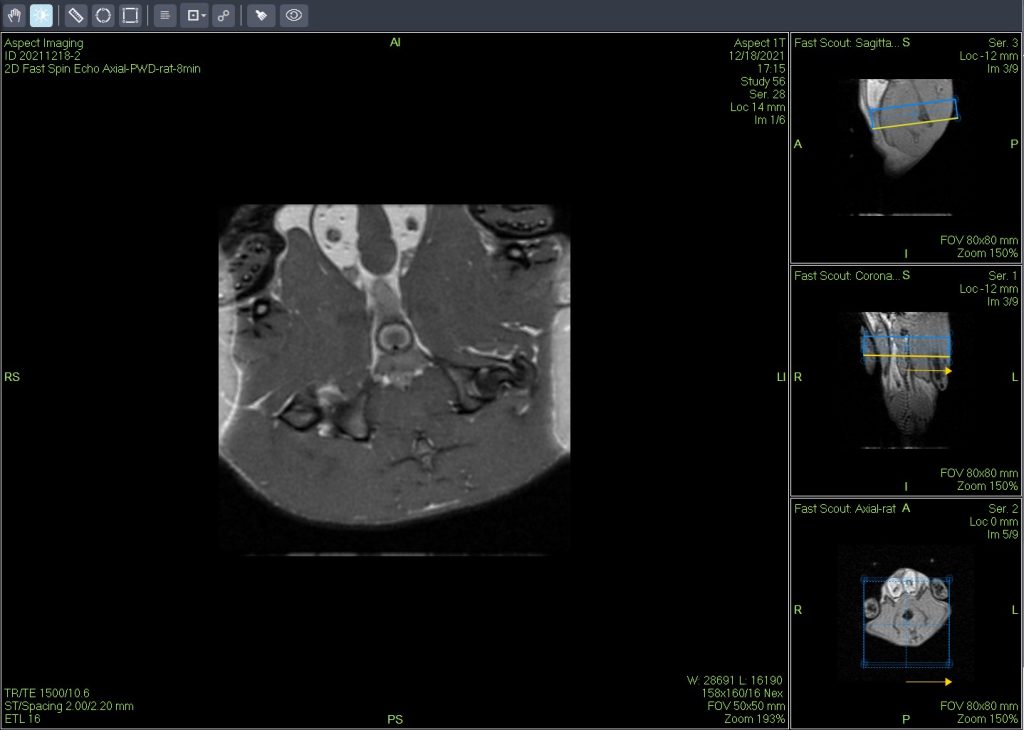

小动物磁共振成像(MRI)是一种强大的非侵入性工具,可用于检测临多种病变。

一个新的紧凑型高性能小动物磁共振成像平台(M3),该系统使用一种新的磁铁设计和一套相关的软件,降低了小动物磁共振成像仪的成本和复杂性。

小鼠皮下肿瘤MRI造影成像效果与造影剂代谢过程研究。

使用仪器: 小动物核磁共振成像仪NM20-060H-I 其他相关应用: 核磁共振造影剂弛豫率分析造影剂分析案例 核磁共振成像与分析技术在生命科学领域应用解决方案